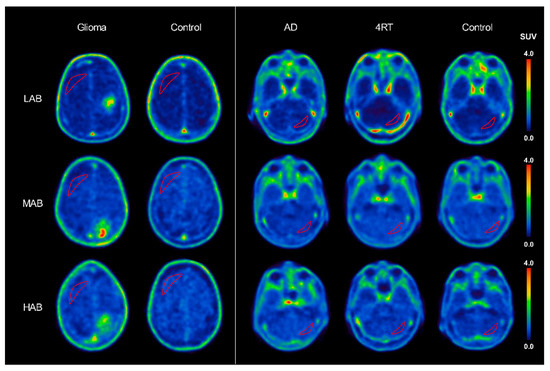

2.2. [18F]GE-180 Binding in a Comparison of rs6971 Polymorphism Subgroups

2.2.2. Disease Groups

Glioma

4RT

AD

2.3. [18F]GE-180 Binding in Frontoparietal and Cerebellar Pseudo-Reference Tissues in the rs6971 Polymorphism Subgroups

2.3.1. LABs

2.3.2. MABs and HABs